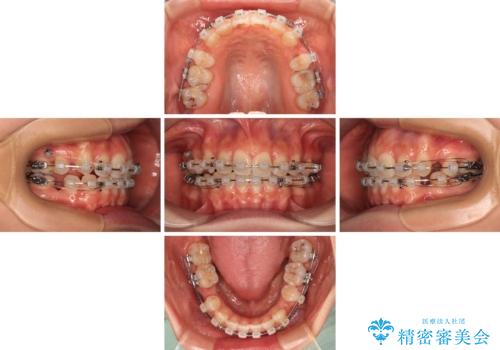

- 矯正装置

- クリアブラケット

- 治療期間

- 2年4ヶ月